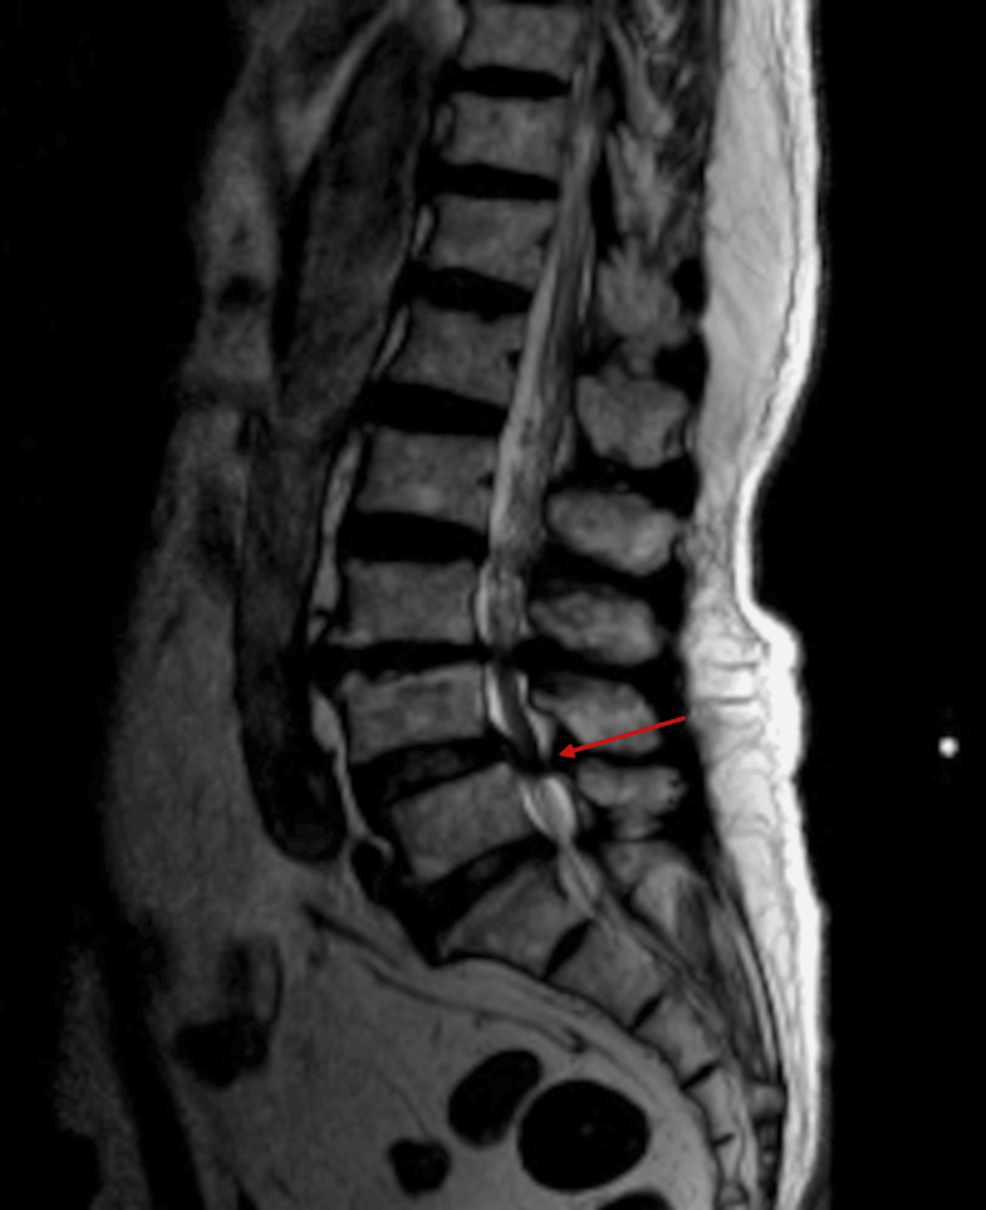

Lumbar spinal interventions, procedures performed in the lower back to address pain or other spinal issues, often involve positioning patients in a way that could potentially increase the risk of aspiration. While the case report doesn’t detail the specific intervention performed, the positioning and potential for post-procedure discomfort could contribute to aspiration. The report serves as a reminder that even relatively common procedures can carry unexpected risks.